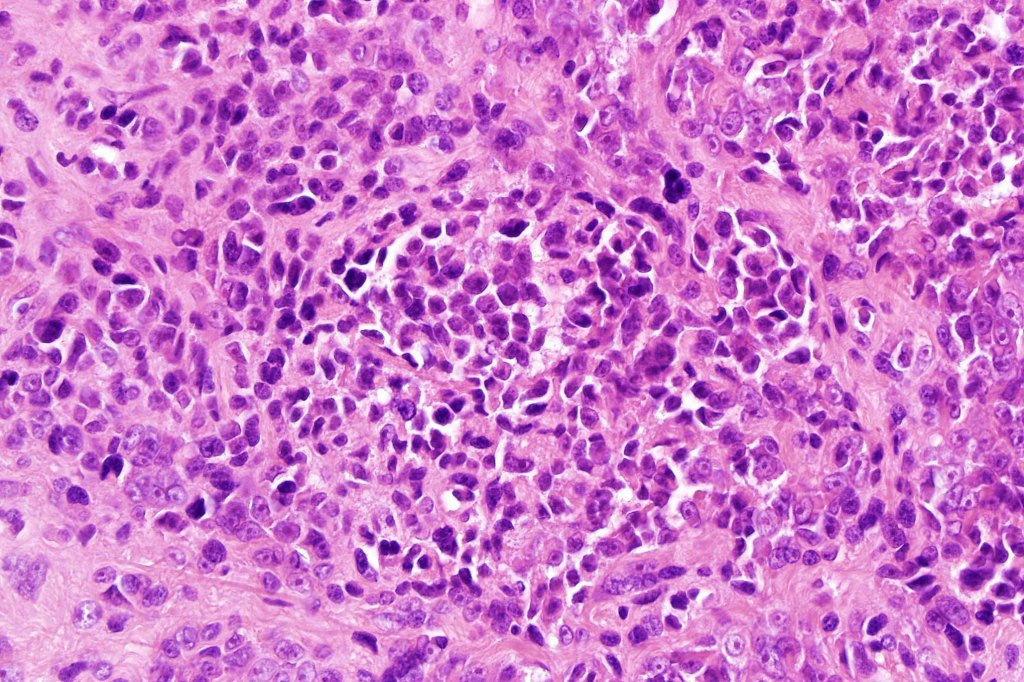

A rare variant of nevoid melanoma wherein the tumor cells have scant cytoplasm, and basophilic, hyperchromic nuclei mimicking type B nevus cells. Typically, the tumor cells are positive for S100, Mart-1 & HMB45. It is of no prognostic importance. It is one of the more often encountered melanoma variants in giant congenital nevi & can be mistaken for a congential nevus if the lesion is dismissed as benign at scanning magnification. In the absence of clinical history in metastatic lesions, the differential diagnoses of lymphoblastic leukemina/lymphoma, neuroendocrine carcinoma, small cell carcinoma, neuroblastoma, malignant perihperal nerve sheath tumor & Ewing’s sarcoma can be excluded with appropriate immunohistochemistry. Exceptionally small cell melanoma may express neuroendocrine markers